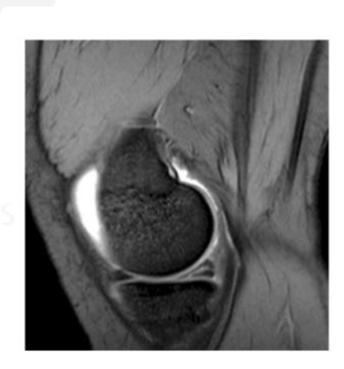

Meniscal Tear Identification

What pathology is seen in this MRI of an 18-year-old male who twisted his knee?

- Posterior horn meniscal tear

- Bucket-handle meniscal tear

What is the significance of the double PCL sign?

- Indicates bucket-handle meniscal tear

What does the white arrow indicate in this image?

- Posterior meniscus horn

What is the diagnosis shown in these images?

- Posterior meniscus horn tear